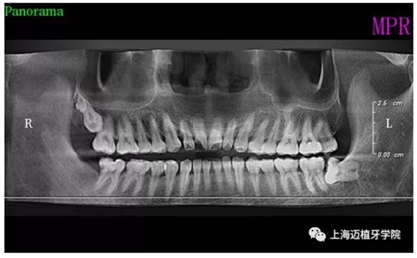

術(shù)前全景片

主訴:前門外傷牙根折要求修復(fù)?現(xiàn)病史:前門牙外傷,劈裂至根部,無法固定及其他修復(fù),要求種植?檢查:11牙冠2/3缺損,唇腭向劈裂,唇部紅腫。 CT示根折, 骨寬度9.47mm,距鼻底12.34mm,Ⅲ類骨。 口腔衛(wèi)生一般